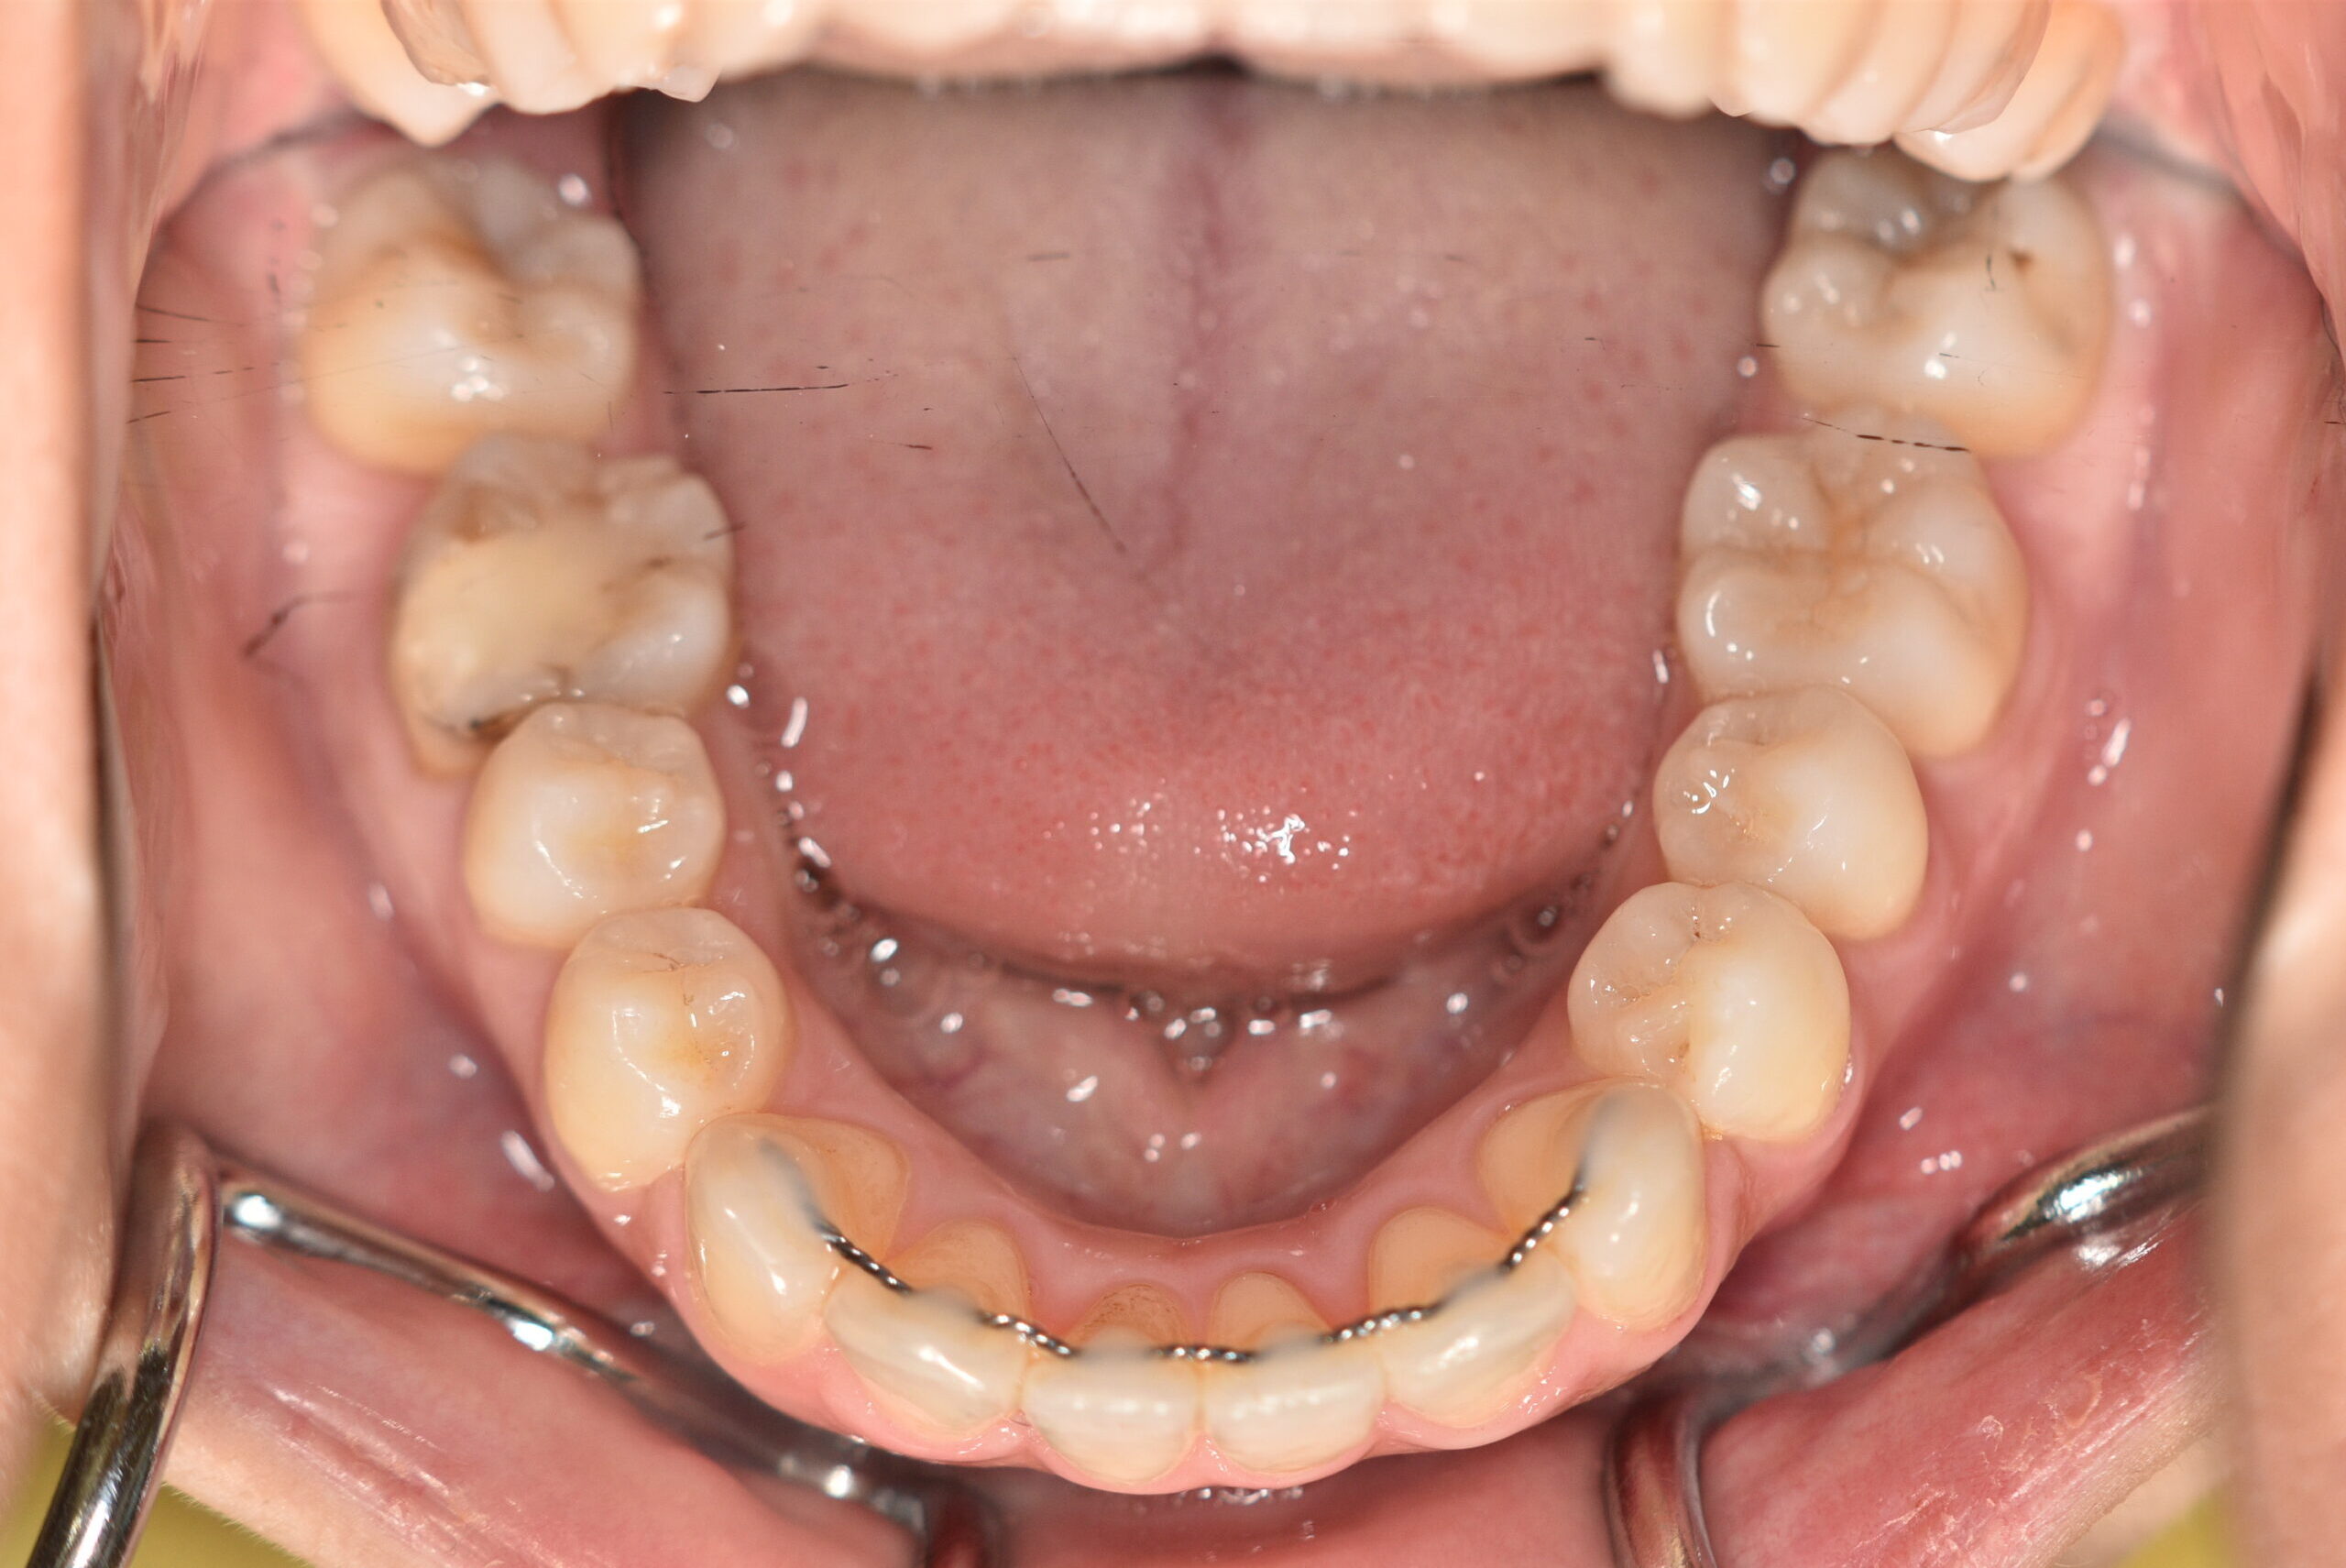

動的治療終了時

症例 症例 症例 症例

治療としては、上顎左右第1小臼歯を抜歯し、セルフライゲーションブラケット装置(デーモンシステム)で歯の配列を行いました。

同時に顎間ゴムにて咬合関係の改善を行いました。

この際、上顎に歯科矯正用アンカースクリューを設置し上顎前歯部後退時の土台としました。

治療期間は、2年11ヶ月でした。